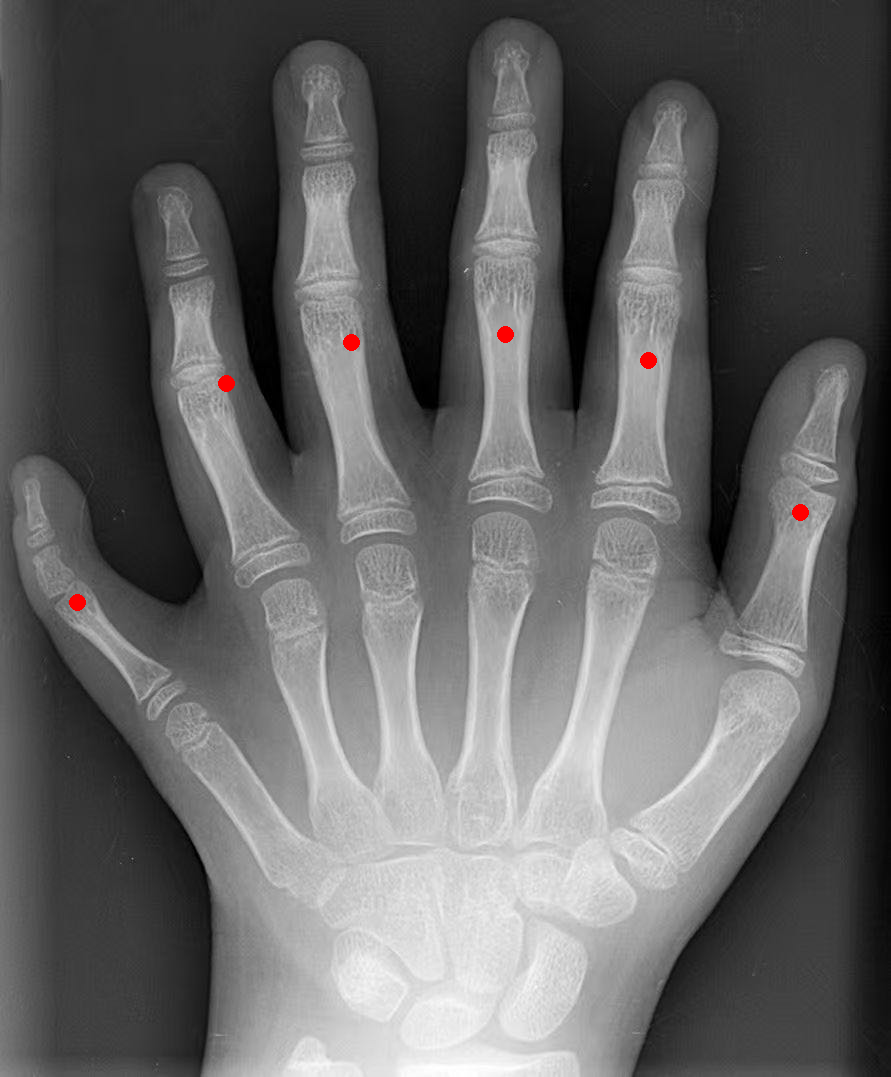

数手指:给一张手部 X 光片,让模型用坐标标出所有手指的位置。模型准确识别并标注了 6 个手指(包括左右两侧拇指和中间 4 个手指)